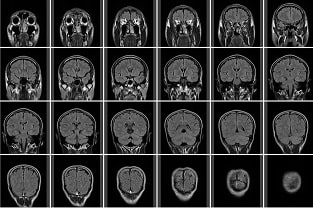

CTスキャン像

神経膠腫(グリオーマ)の星細胞腫では正常脳と等密度であることが多いのですが、造影剤の増強効果で腫瘍が明らかとなります。

神経膠腫(グリオーマ)は境界が不規則で不鮮明です。

乏突起膠腫は石灰化を伴うため高密度に映ることが多い。

髄膜腫は造影剤の増強効果で腫瘍が明らかとなります。

転移性腫瘍は腫瘍内部の壊死により低密度に映ることが多い。